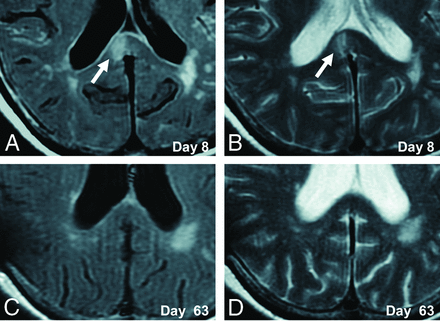

A 70-year-old woman presented with poor-grade SAH (Hunt and Hess grade 4). CT revealed Fisher group 3 SAH, and MRA demonstrated a 5-mm-diameter aneurysm on the anterior communicating artery. The patient underwent aneurysm coiling on day 2. This patient developed DCI and received regional arterial infusion of fasudil hydrochloride hydrate 3 times. She also developed hydrocephalus and underwent ventriculoperitoneal shunting. The patient had mild disorientation and was discharged home with an mRS score of 3. Although no abnormality was evident on DWI in this patient on admission (Fig 2A), a high-signal area appeared in the splenium of the corpus callosum on SAH day 7 (Fig 2B). The lesion gradually faded and had completely resolved by day 63 (Fig 2C–F). This change was thought to represent CLOCC and was also observable on FLAIR and T2WI (Fig 3).

Serial FLAIR and T2WI in an illustrative case. CLOCC (white arrows) are observed in the splenium on FLAIR and T2WI on day 8 (A and B) and resolve by day 63 (C and D).